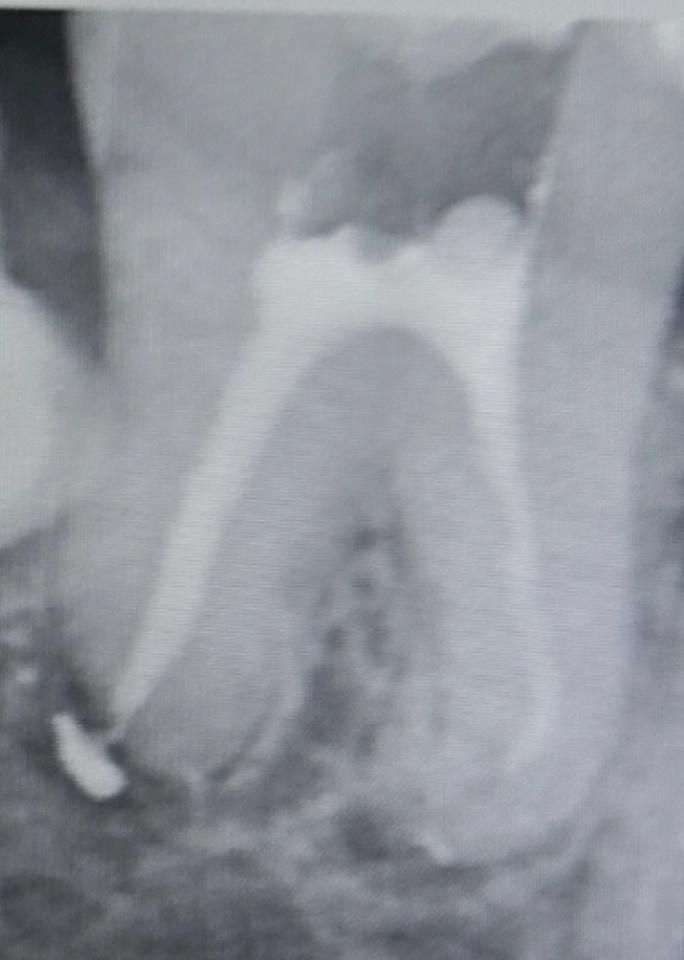

신경치료 마무리 했는데 잘 안된걸까요?

마무리하고 찍은 엑스레이사진인데

한쪽 재료가 넘친건 그렇다 하더라도

다른쪽이 끝까지 안된 것 같은데요 ㅠ

신경관은 눈에 보이는것처럼 무조검 치아 끝까지 잇는게 아닙니다. 사진상으로 보면 신경치료는 잘된거 같습니다.

1. 용츌된 것은 거타퍼챠는 아니고 실러로 큰 악영향은 없습니다

2. 다른쪽도 크게 부족하게 충전된 것은 아닌 것으로 보입니다